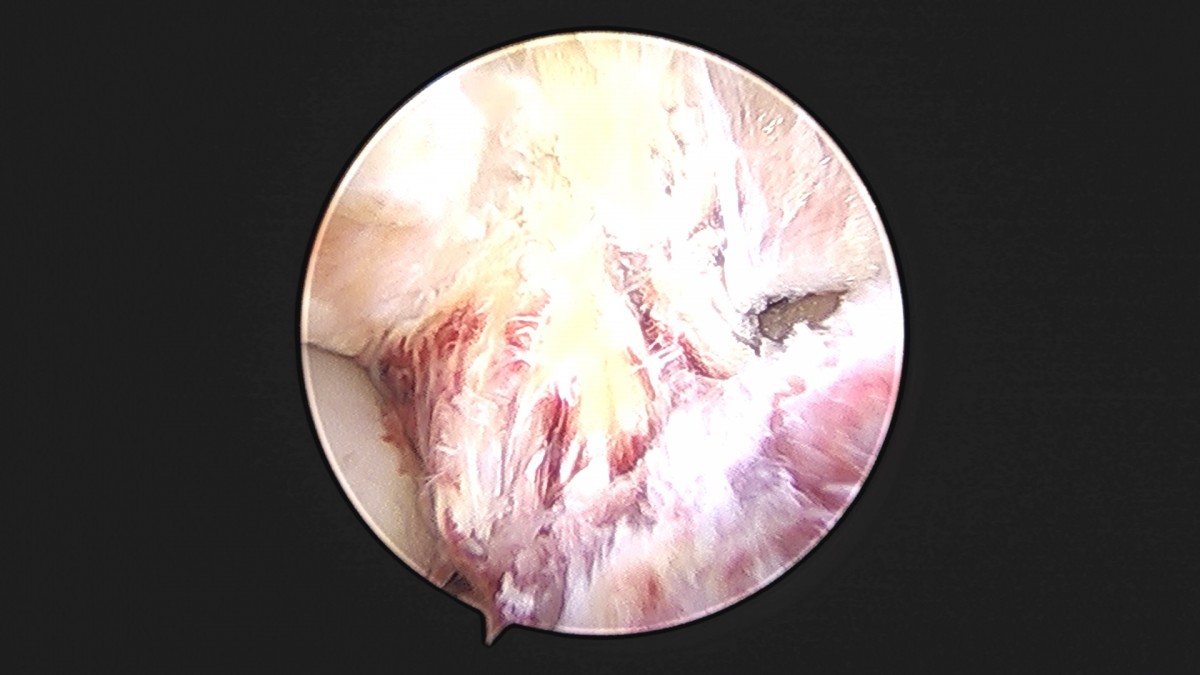

이재상원장님 발목 인대 봉합술 박찬O 환자

dae765e4d9ac96aee867c9d6292d8784_1758007284_4686.jpg